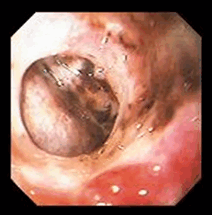

Рис.1. Перфорация язвы ДПК

Лапароскопически оперированы 2 больных. Использовали собственный вариант ликвидации перфорации ППДЯ из 3 проколов передней брюшной стенки (патент №2397727 RU, 2008). Методика заключалась в тампонировании перфорации прядью большого сальника одной нитью (см. рисунок, а). Рисунок 1. Этапы лапароскопической ликвидации перфоративной пилородуоденальной язвы. Объяснения в тексте. Периферический конец нити далее использовался в качестве держалки. Ей же фиксировался сальник к стенке кишки непрерывным обвивным швом (см. рисунок, б). В последующем оба конца нити укреплялись титановой клипсой (см. рисунок, в).